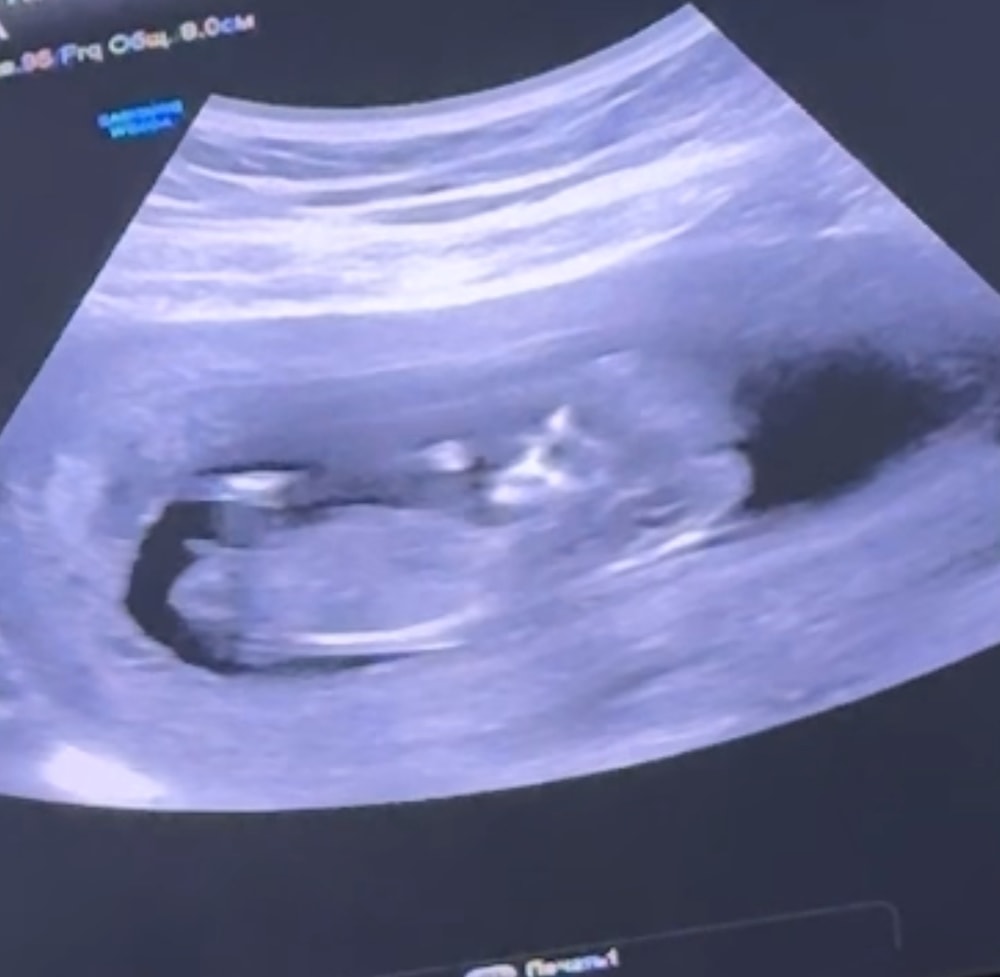

Какой пол вы тут видите ?

Да там писюн огромный, конечно мальчик

Александра, ну или если срок маленький и это половой бугорок, то тоже мальчуковый

100 мальчишка у вас

Мальчик

11+5 фото узи Доплер